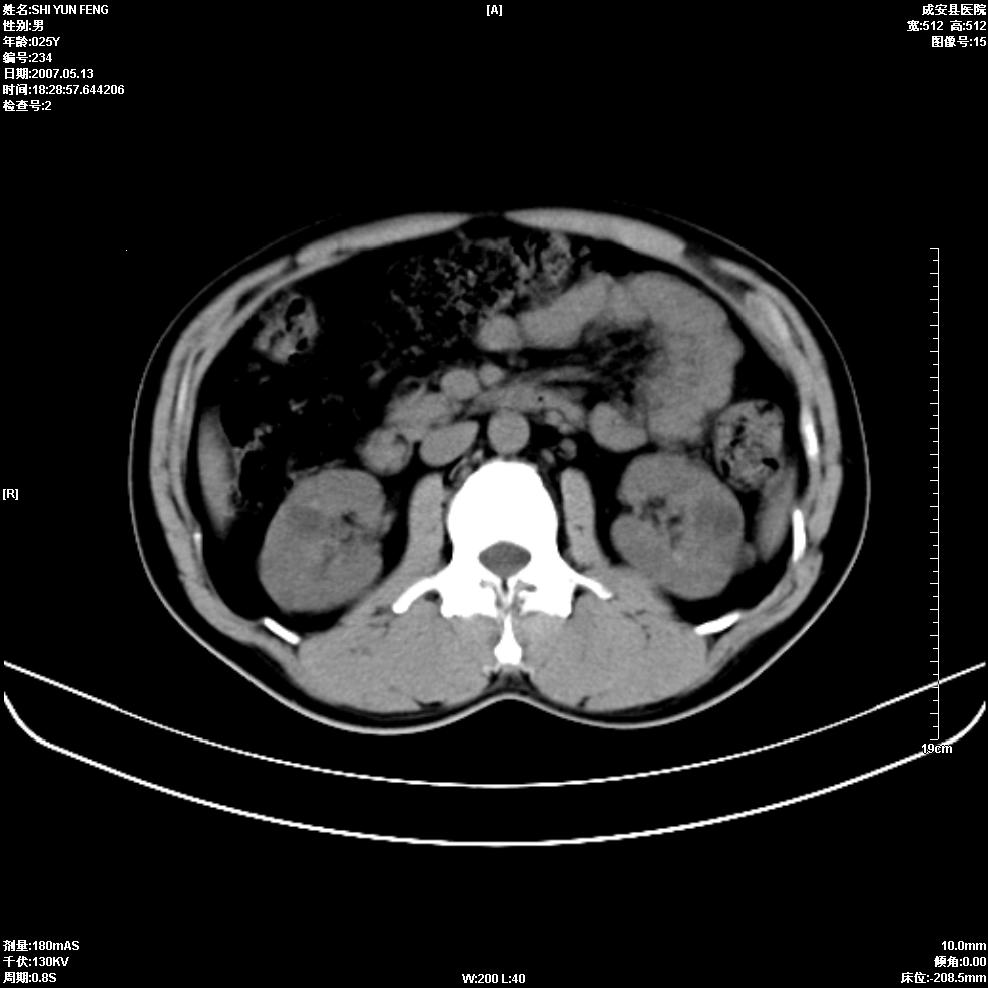

以下是引用zhangzhongshou在2007-5-16 7:36:00的发言:[br]多发性肾囊肿,左肾多发结石。不是多囊肾,楼主箭头所指多考虑左肾囊肿内结石或钙乳,髓质海绵肾不完全除外。[br][br][本贴已被 zhangzhongshou 于 2007-5-16 7:37:18 修改过][br][br][本贴已被 zhangzhongshou 于 2007-5-16 18:15:09 修改过]